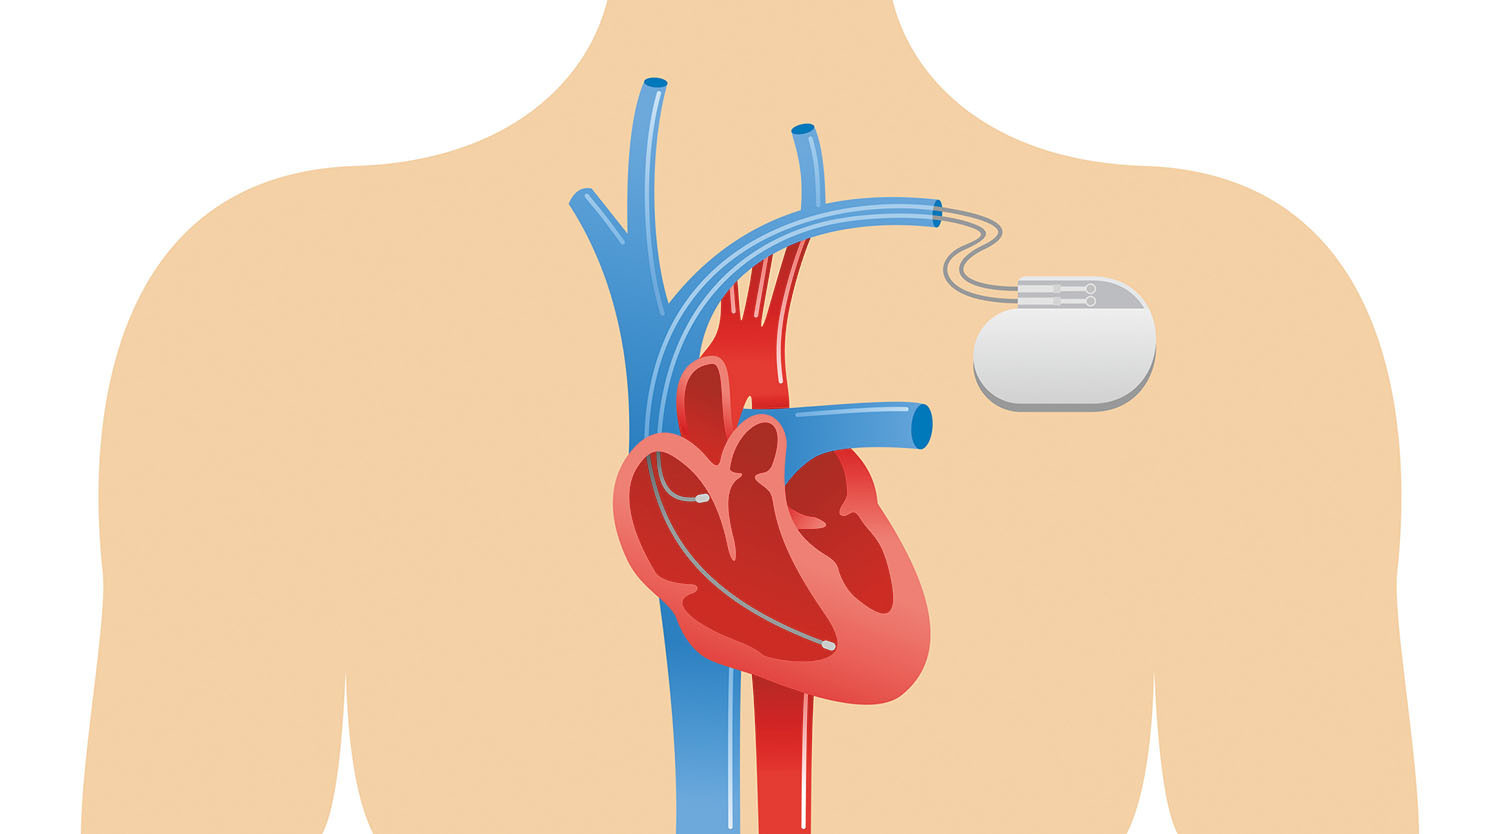

A pacemaker is a medical device that helps regulate abnormal heart rhythms. It is surgically implanted in the patient’s chest. It sends electrical impulses to the heart to make it beat in a regular pattern. A pacemaker can also be referred to as a cardioverter-defibrillator (CVR). It consists of a small battery-powered generator and leads that are implanted into the heart. This generator transmits electrical impulses to the heart to maintain a consistent heartbeat. Pacemakers are commonly used to treat conditions such as bradycardia (slow heart rate) and heart block. Pacemakers offer various benefits to individuals with heart conditions, helping them to improve symptoms and reduce complications. However, a regular visit to a cardiologist is mandatory for proper evaluation and keeping track of your prognosis.

A - Pacemaker implantation is typically performed under local anaesthesia. The surgeon makes a small incision near the collarbone and inserts the leads into the heart through a vein. The generator is then placed under the skin and connected to the leads. The procedure usually takes a few hours, and most patients can go home the same day or the following day.